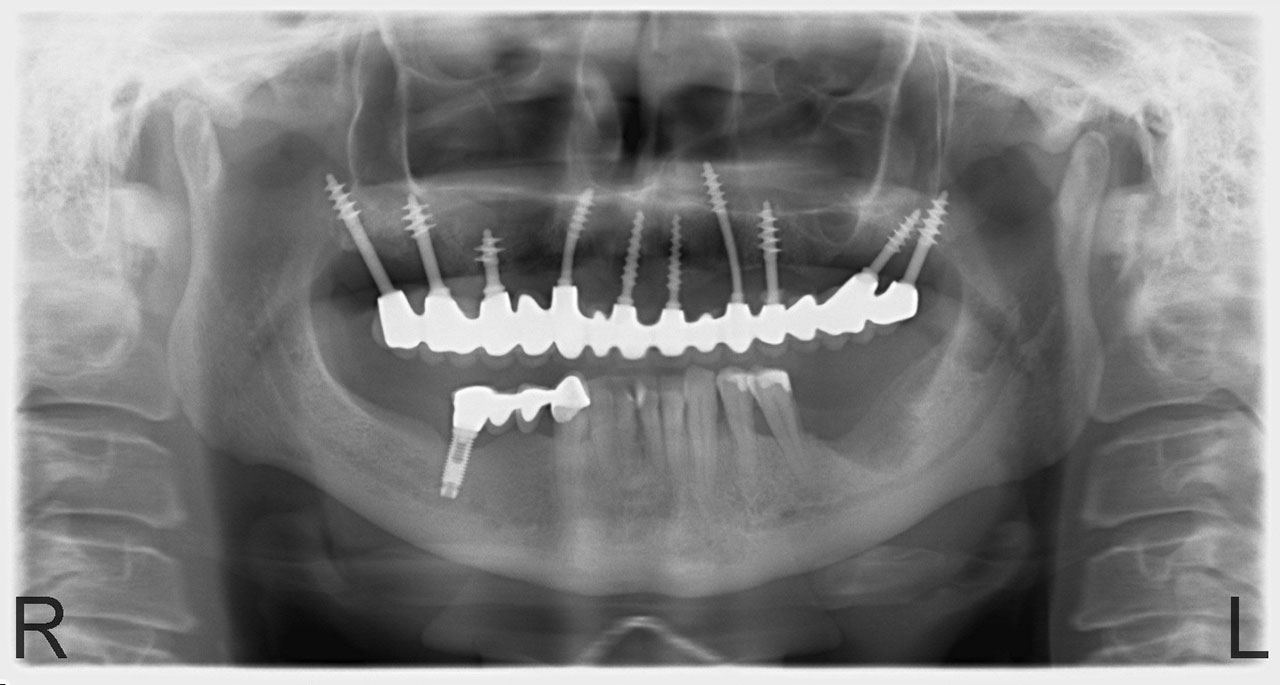

Sikerét mindenekelőtt a gyorsaságának köszönheti, hiszen a mai rohanó világban kinek van ideje, kedve fogatlanul otthon ülni heteket, hónapokat a fogpótlásra várva? Az Ihde implantációs eljárás során a páciens azonnal, de legkésőbb 72 óra múlva egy rögzített (tehát nem mozgó, nem kivehető) pótlással hagyja el a rendelőt. Ez az egyedülállóan gyors eljárás annak köszönhető, hogy azonnal tudunk implantálni szinte bárhova, akár foghúzás után is, továbbá a művelet nem jár nagy feltárásokkal, nincs szükség csontbeültetésre, így a gyógyulás folyamata is nagyon gyors és a beültetés technikájának köszönhetően maximum 72 óra múlva a korona is feltehető. Tehát ennyi idő alatt foga lesz a betegnek és az implantátum azonnal terhelhetővé is válik.

Az eljárás mellett szól az is, hogy nagyon biztonságos. A cég adatai alapján a beültetett implantátumok 98.2%-a sikeres. Az azonnali terhelésű implantátumokkal rögtön, akár foghúzás után is szinte bárhová lehet implantálni, bárkinek, legyen szó cukorbeteg, dohányos, vagy akár csontritkulásban szenvedő páciensről. Ennek köszönhető, hogy a betegek 99%-ánál alkalmazható a módszer.